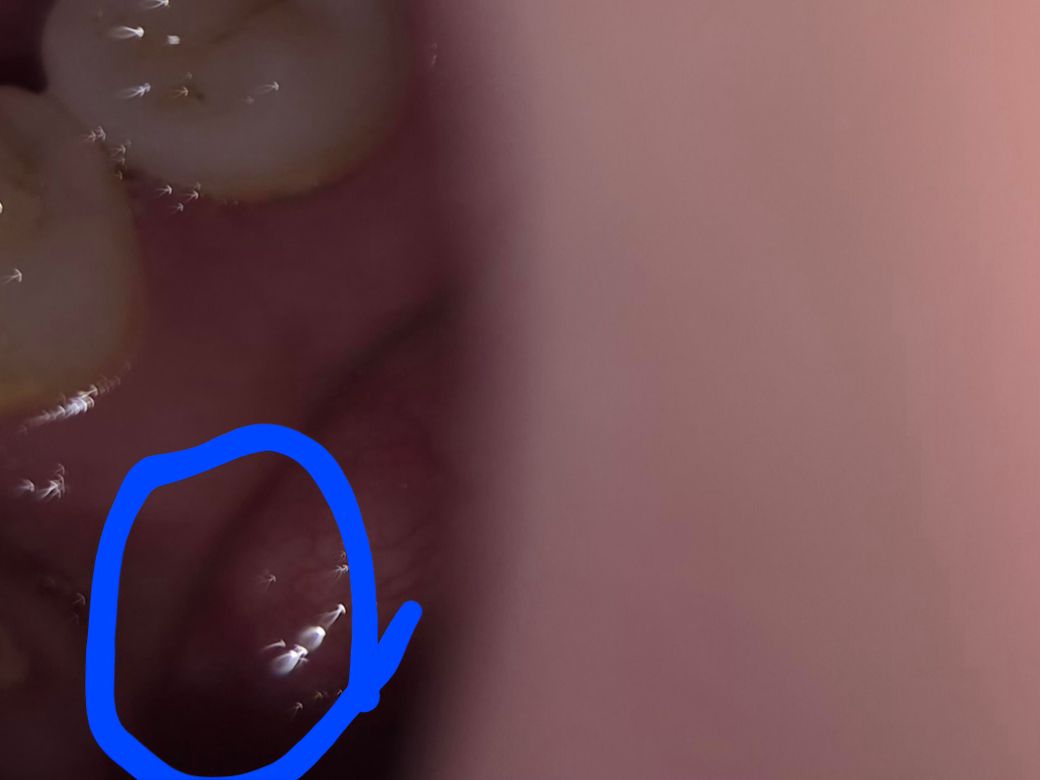

• 아랫잇몸 치아 안쪽 잇몸에 혀로 이물감이 느껴지는 흰색 반점이 보이는데요 딱히 통증도 없고 안쪽이라 언제 생겼는지도 아니면 원래부터 있었는지도 잘 모르겠는데 혹시 구강암일까요? 아니면 다른 질환일까요? 그것도 아니면 그냥 뼈일까요 저 부위에도 뼈가 있을수 있나요?

• 2번 째 사진

사진이 자세하지 않아서 정확히는 모르겟지만 하악골 융기가 아닐까 생각됩니다. 문제가 잇는건 아니고 잇몸뼈가 튀어 나온거 같습니다.

아랫잇몸 치아 안쪽 잇몸에 혀로 이물감이 느껴지는 흰색 반점이 보이는데요 딱히 통증도 없고 안쪽이라 언제 생겼는지도 아니면 원래부터 있었는지도 잘 모르겠는데 혹시 구강암일까요? 아니면 다른 질환일까요? 그것도 아니면 그냥 뼈일까요 저 부위에도 뼈가 있을수 있나요 -> 뼈는 아니고요 악성병소의 양상도 아닙니다 치과가서 조직검사 해보시기 바랍니다